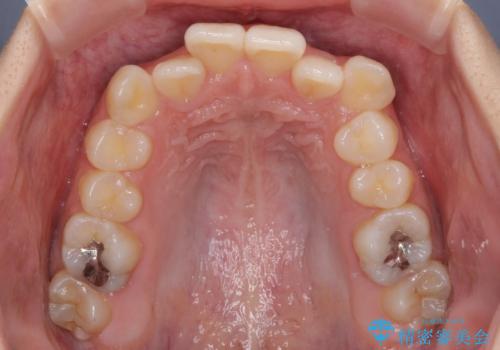

デコボコと八重歯の目立つ前歯 ワイヤー装置による抜歯矯正

- 上下前歯のデコボコと八重歯を気にして来院された患者様です。

叢生を解消する際に出っ歯とならないようにするために、上下左右の小臼歯計4本を抜歯することとしました。